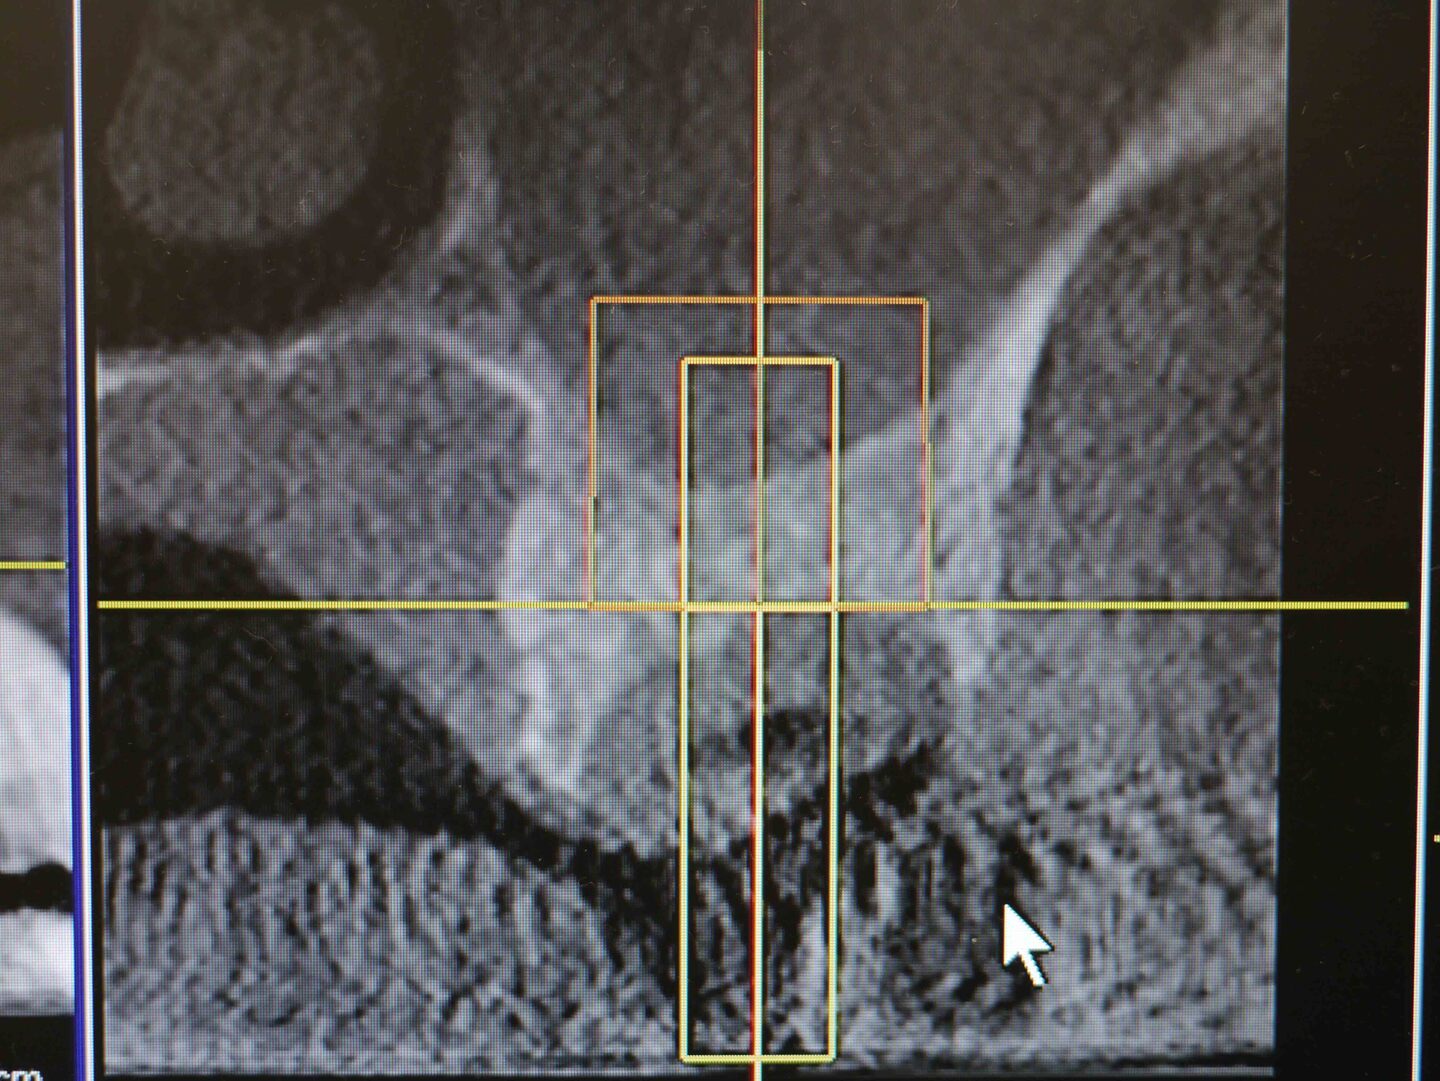

CT画像

上顎洞底の骨の厚さが右上7番で最低4mm、6番で2mm程度

埋入予定の骨を側面(頬側)から見たCT画像

平成24年9月 手術前のCT画像